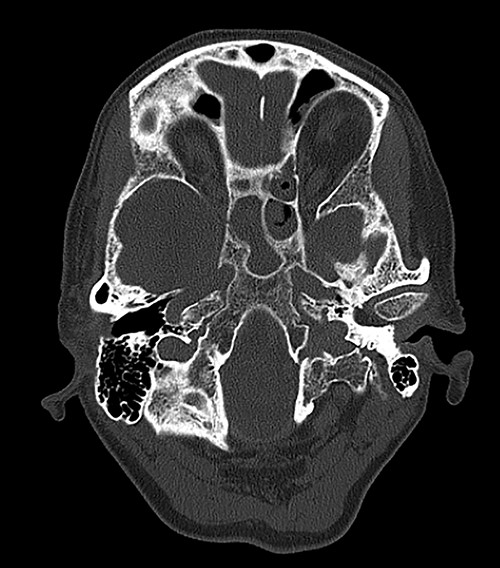

Computed tomography (CT) of the head revealed no signs of meningeal or intracerebral enhancement to suggest an intracranial abscess or cerebritis (Fig. 1).

CT head revealed no signs of meningeal or intracerebral enhancement to suggest an intracranial abscess or cerebritis, but it suggested significant opacification in the paranasal sinuses, particularly in the ethmoid and sphenoid sinuses, most likely indicating a minor post-operative haemorrhage.

Once the diagnosis of SIADH was established, the main goal was to investigate causes that could have generated the electrolyte imbalance. Any central nervous system disorder, such as meningoencephalitis, cerebral tumours, cavernous sinus thrombosis, hydrocephalus, multiple sclerosis, subarachnoid haemorrhage or head trauma, was excluded by the CT head scan. Pulmonary conditions, such as bronchogenic small cell carcinoma, pneumonia, tuberculosis, abscess and aspergilloses, were considered but were ruled out by a clear chest X-ray. As the patient had mild abdominal discomfort, upper gastrointestinal endoscopy and abdominal US were performed, and we excluded any gastrointestinal carcinoma. Potential endocrine issues, such as adrenal insufficiency and hypothyroidism, were part of the differential diagnosis but were excluded after a positive short Synacthen and findings of normokalaemia and normal thyroid function tests. The patient’s regular medication did not have any drugs that stimulate ADH release of potentiate its actions, or ADH analogues [4]. However, the small dose lansoprazole she was taking for her gastroesophageal reflux may have contributed to her hyponatraemia. Vomiting is a symptom of severe hyponatraemia and it is likely that these episodes also had a role in further aggravating her sodium levels through dehydration. Another potential contributing factor could have been the analgesic medication given post-operatively. Hereditary causes were excluded from her medical history. She had no history of pituitary surgery, but the small haemorrhage in her sphenoid sinus, visible on the CT imaging, could have caused an imbalance in the function of her neurohypophysis.